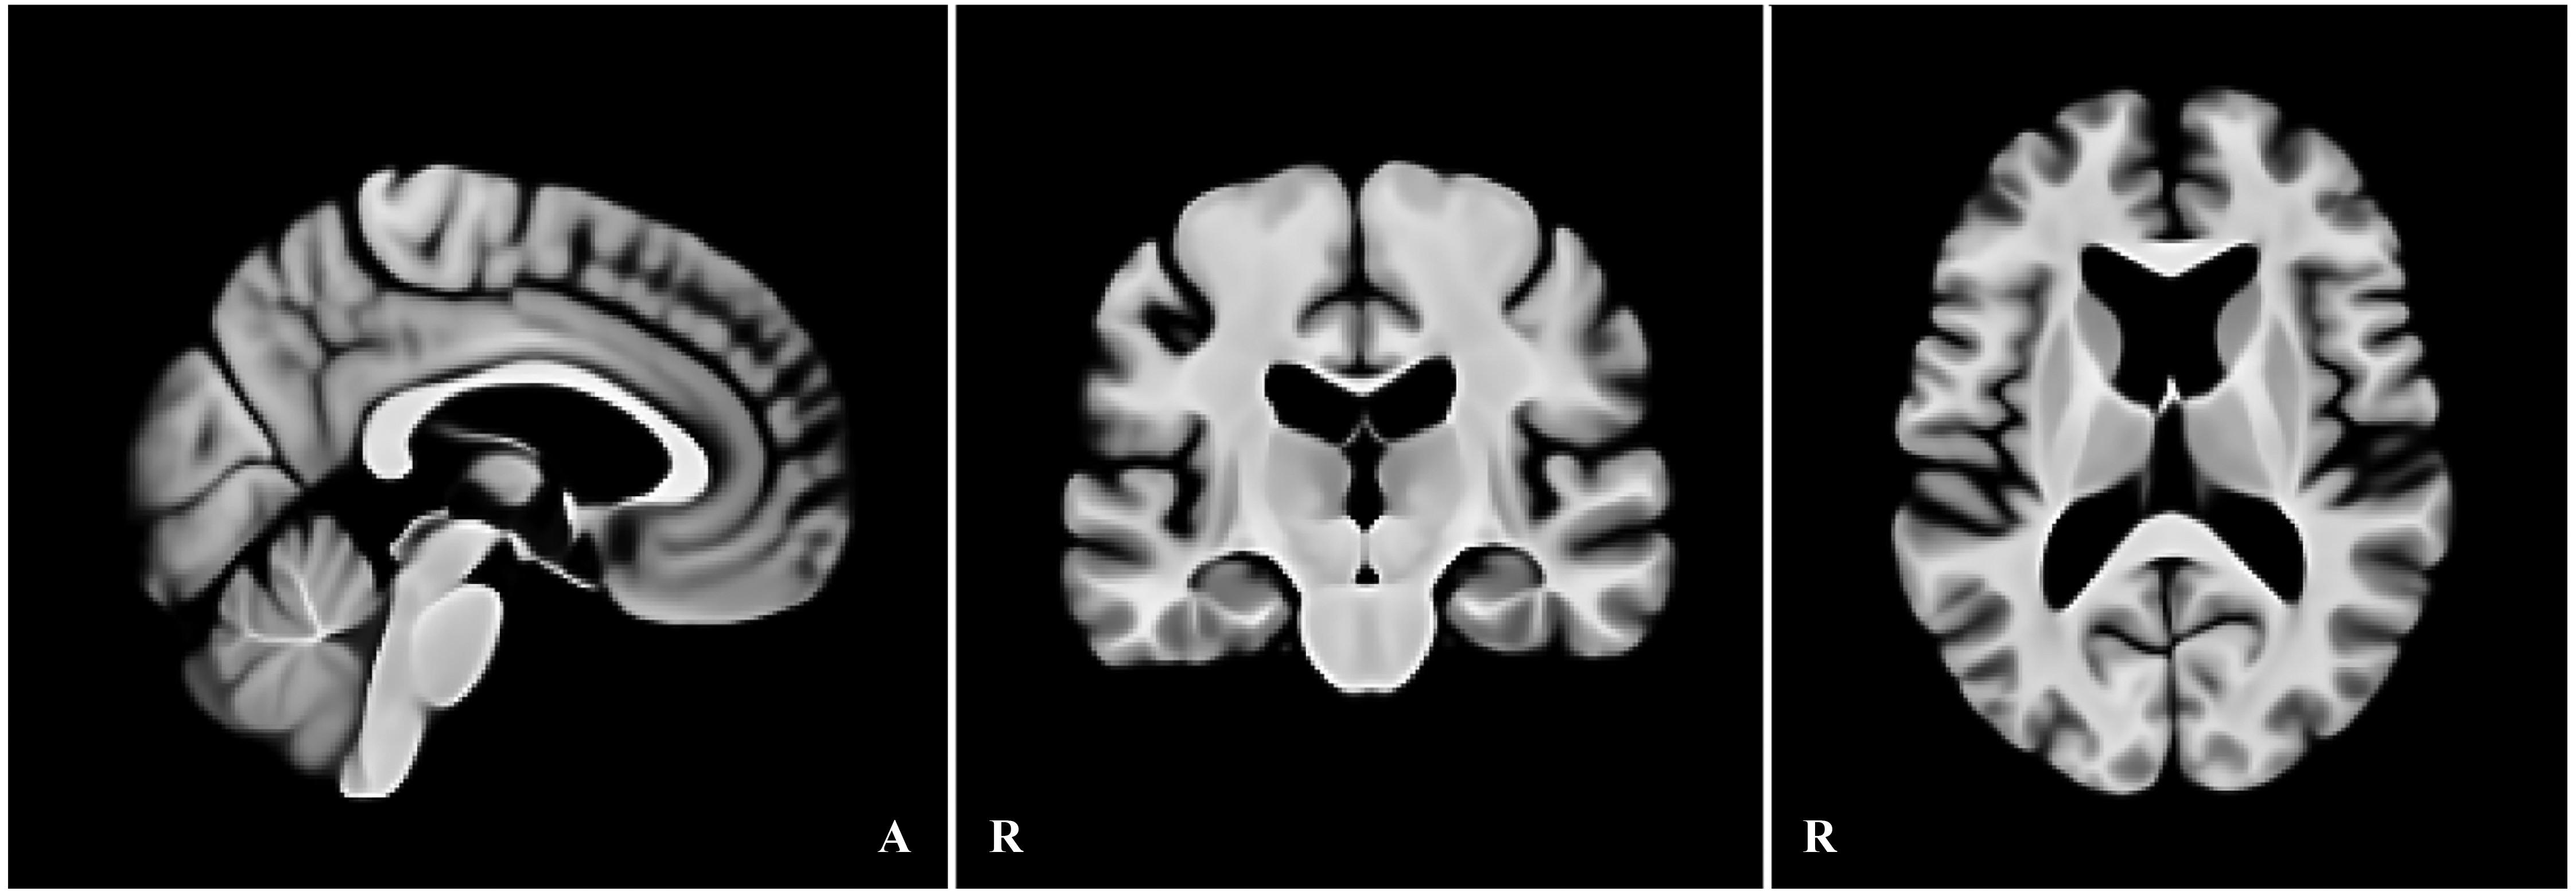

埼玉医科大学脳神経内科の大田一路らによる研究グループが新たな高齢者脳テンプレートを開発 ― 加齢に伴う脳形態の変化をより正確に反映

埼玉医科大学(埼玉県入間郡毛呂山町)脳神経内科の大田一路らによる研究グループはこのたび、高齢者向け標準脳テンプレートを新たに開発した。既存の脳テンプレートであるMNI152と比較して、60歳以降で整合性が向上しており、今後、高齢者の神経変性...